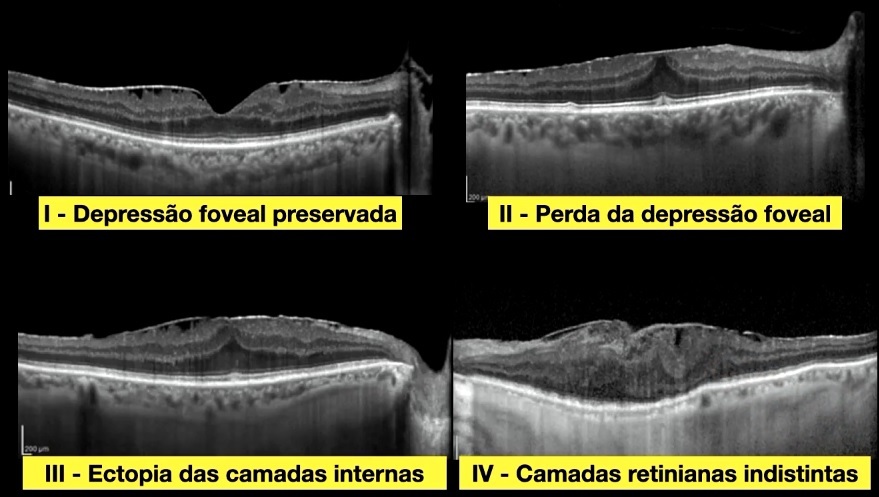

Estágio I: Depressão foveal preservada

Estágio II: Perda da depressão foveal

Estágio III: Ectopia das camadas internas

Estágio IV: Perda da distinção das camadas da retina